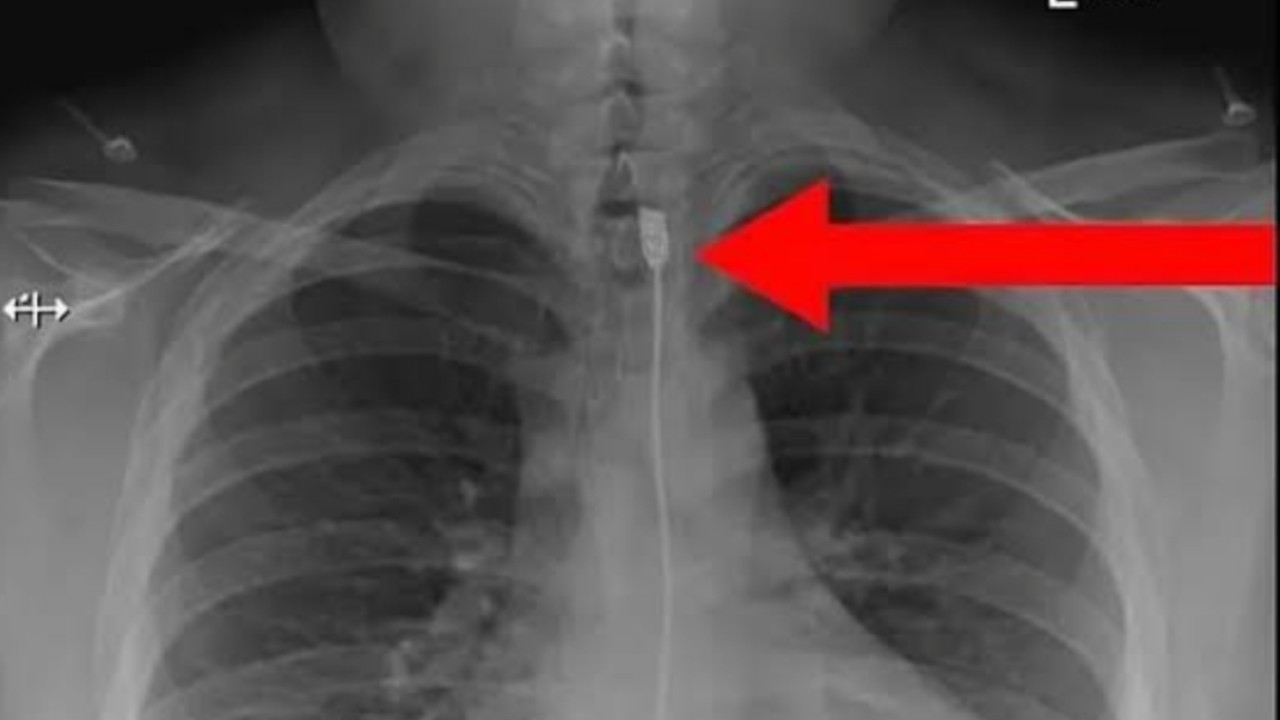

Mereka juga mengunggah foto hasil x-ray pasien, yang memperlihatkan gulungan kabel charger di tenggorokannya.

"Ini adalah kasus terbaru, dari seorang wanita yang menelan kabel charger iPhone sepanjang satu meter. Wanita ini kemudian menghubungi Rescue Team, setelah dia kesulitan bernafas, karena bagian atas kerongkongannya ditutupi kabel charger," jelas tim Ready To Rescure.

"Untungnya kabel itu berhasil dikeluarkan, dan kini pasien tengah dalam masa pemulihan. Sayangnya, dia tidak memberi tahu alasannya mengapa dia menelan kabel charger," pungkas laporan tersebut.